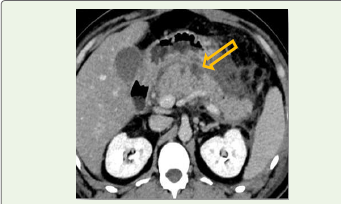

Figure 2:Axial pancreatic-phase contrast-enhanced CT image

demonstrating non-enhancing pancreatic parenchyma (arrow) used for

calculation of percentage pancreatic necrosis.